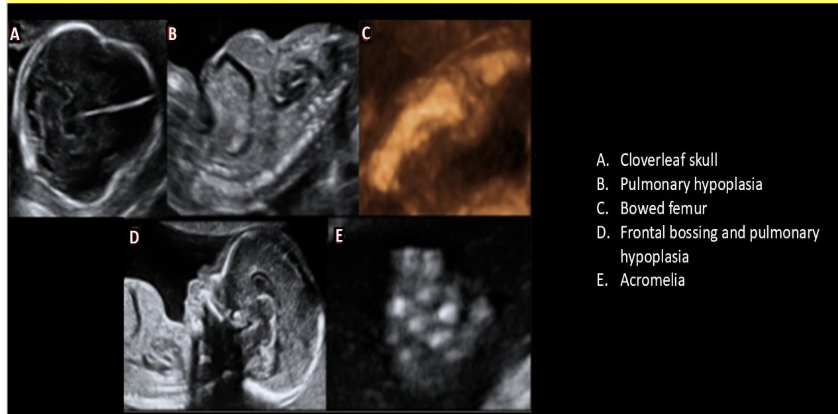

a clover-leaf skull is most commonly assoc w/

d) thanatophoric dysplasia